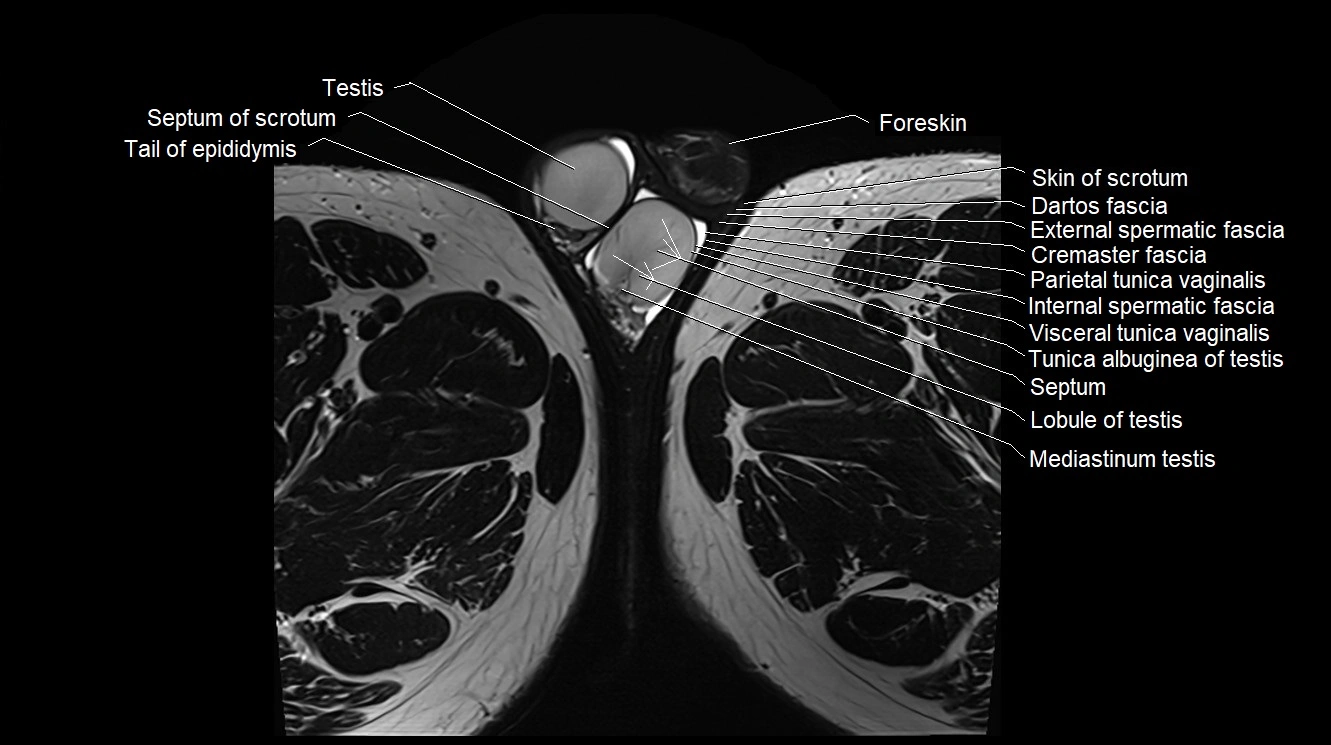

- Cremaster fascia

- Dartos fascia

- External spermatic fascia

- Foreskin

- Internal spermatic fascia

- Lobule of testis

- Mediastinum testis

- Parietal tunica vaginalis

- Septum of scrotum

- Septum of testis

- Skin of scrotum

- Tail of epididymis

- Testis

- Tunica albuginea of testis

- Visceral tunica vaginalis